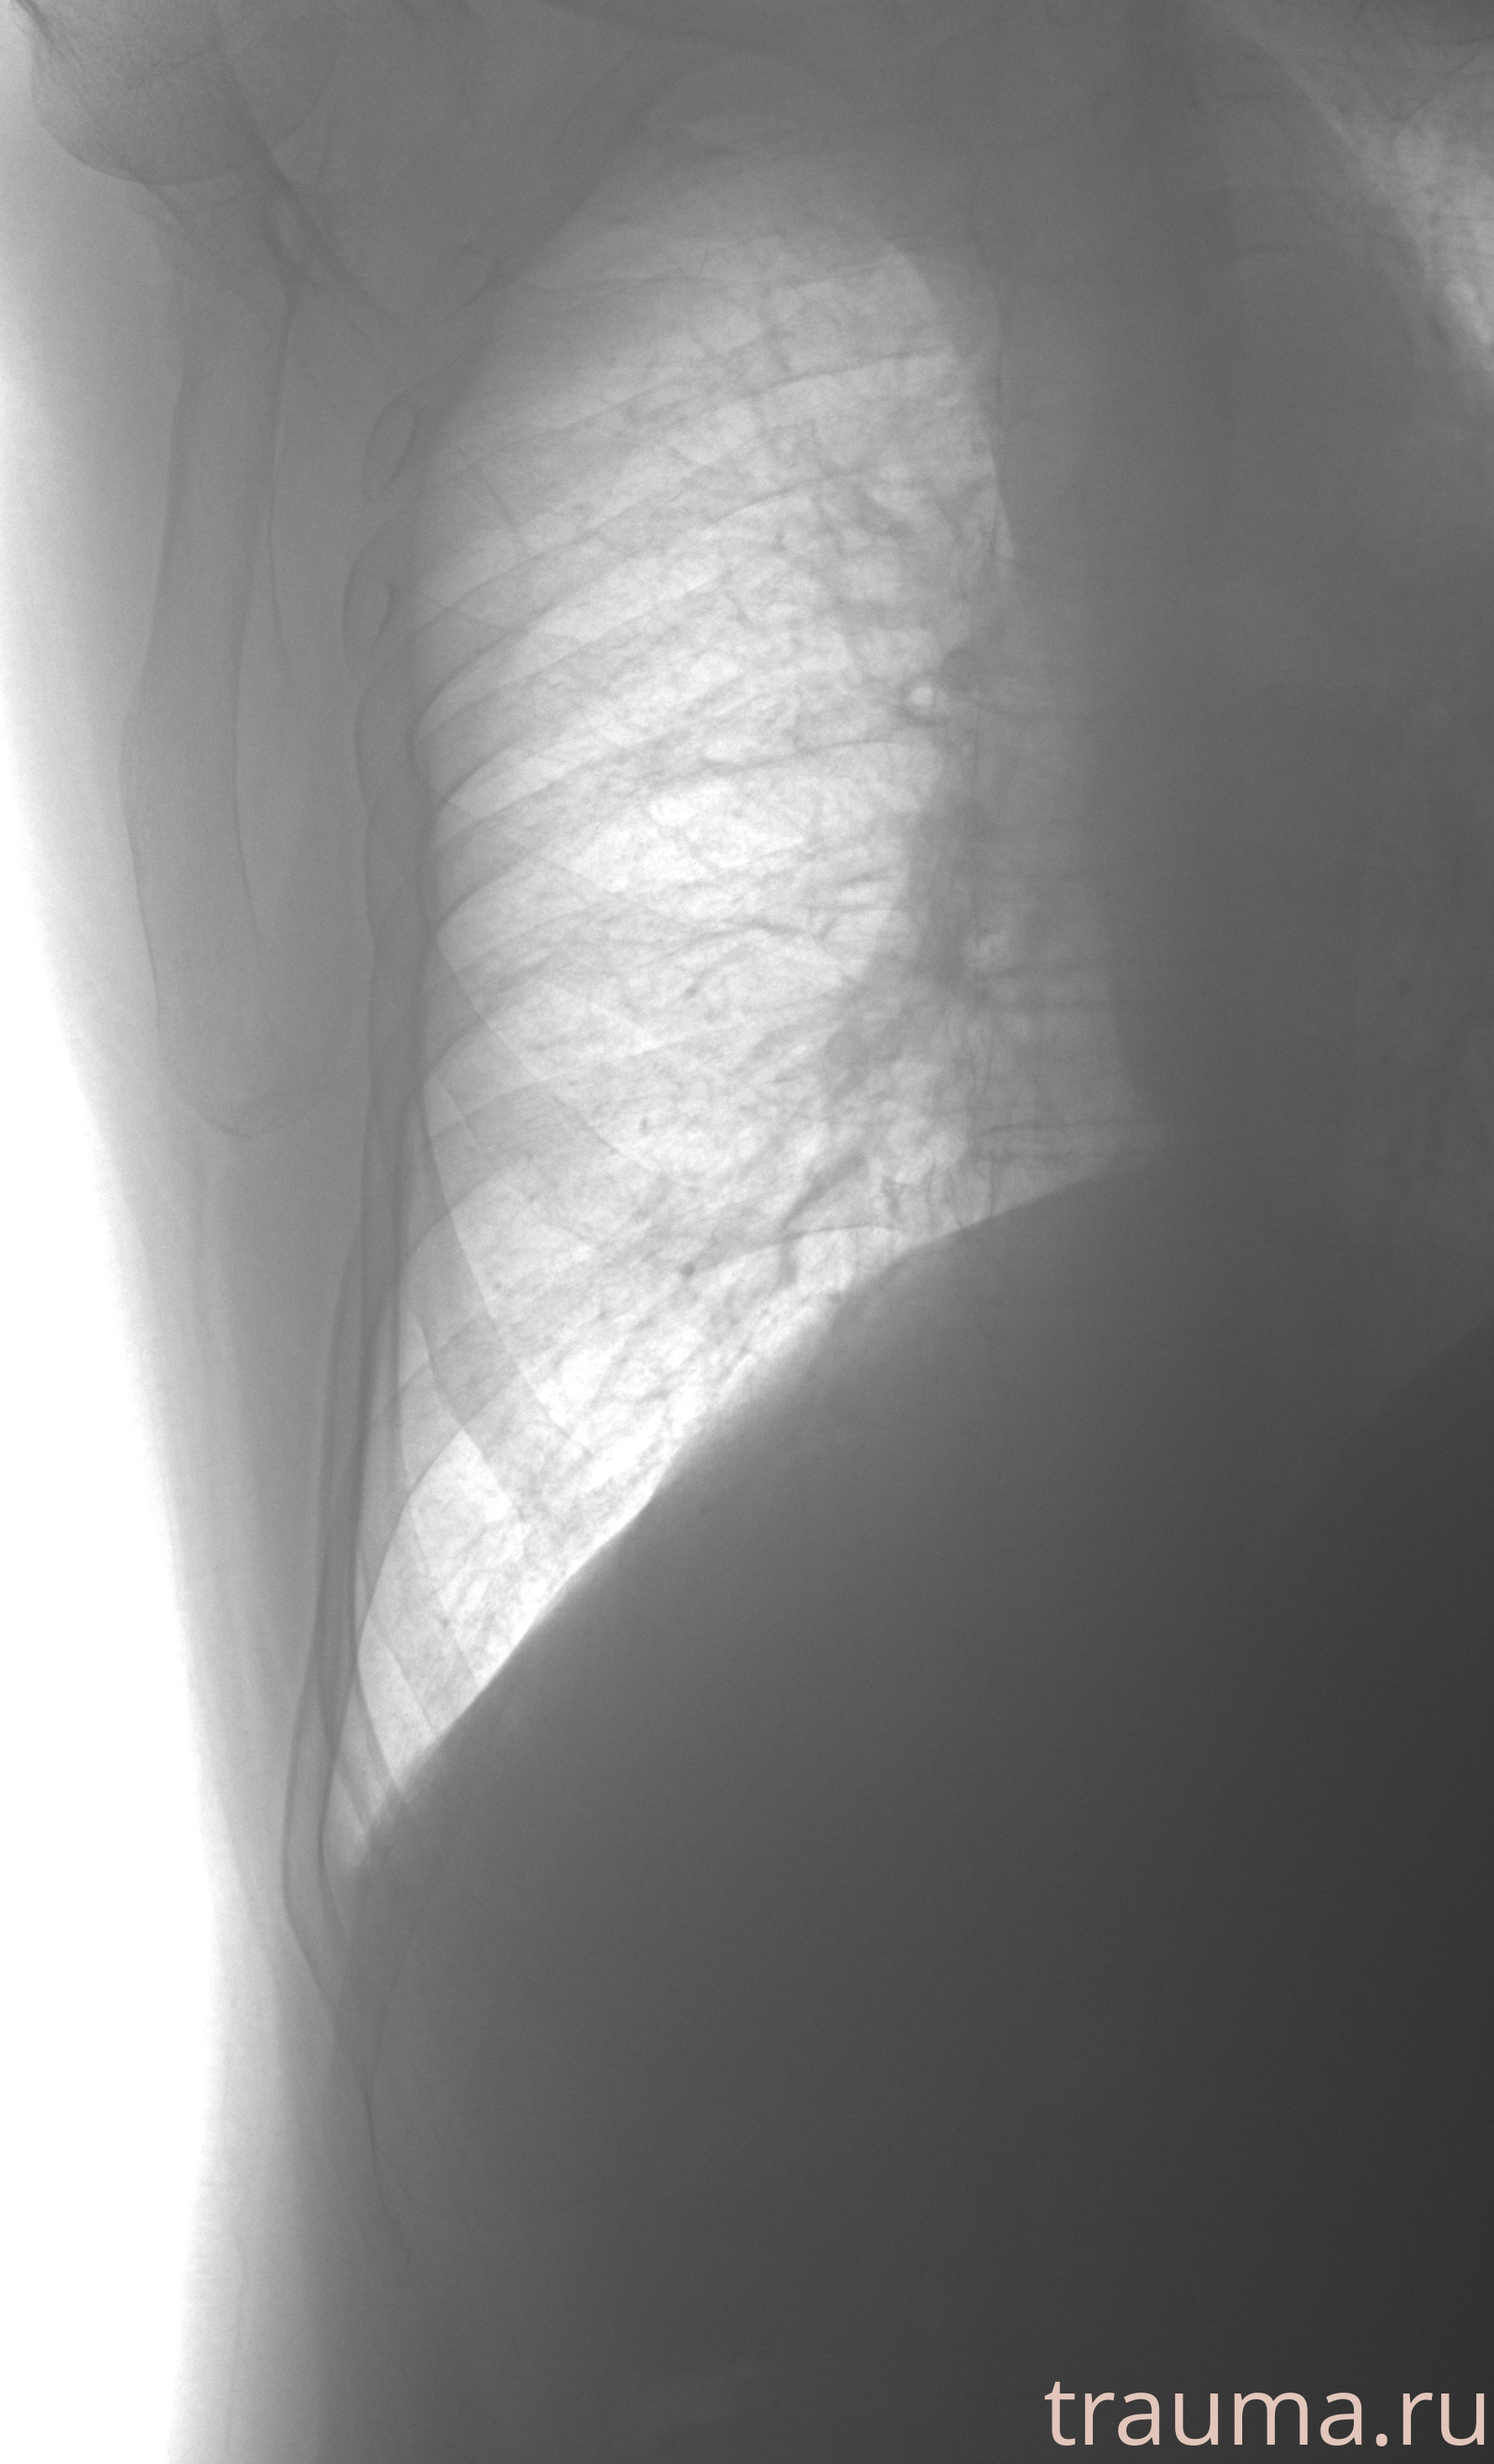

Рентгенограммы

Рентген на дому: по вашему адресу приезжает врач-рентгенолог, травматолог-ортопед с мобильным рентгеновским аппаратом, проводит диагностику травмы или заболевания, делает необходимые рентгенограммы, дает рекомендации по дальнейшему лечению. Получить качественные снимки в домашних условиях возможно благодаря уникальной методике, разработанной МосРентген Центром для института  Склифосовского

Яркость: 1   Контраст: 1   Инвертировать: 0 Увеличение: 1

Перетаскивайте мышь вверх/вниз для контраста, влево/право для яркости. Прокрутка колесом изменяет масштаб. Нажмите Сбросить для возврата к исходному изображению. При увеличении держите мышь в той области, которую хотите рассмотреть.